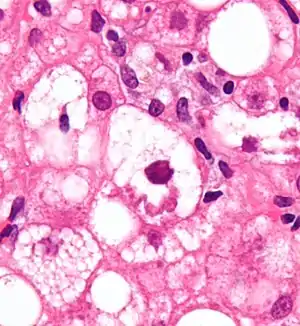

Mallory bodies are highly eosinophilic and thus appear pink on H&E stain. The bodies themselves are made up of intermediate cytokeratin 8/18 filament proteins that have been ubiquitinated, or bound by other proteins such as heat shock proteins, or p62/Sequestosome 1.[5]

Micrograph showing a Mallory body. Original magnification 400X. H&E stain.